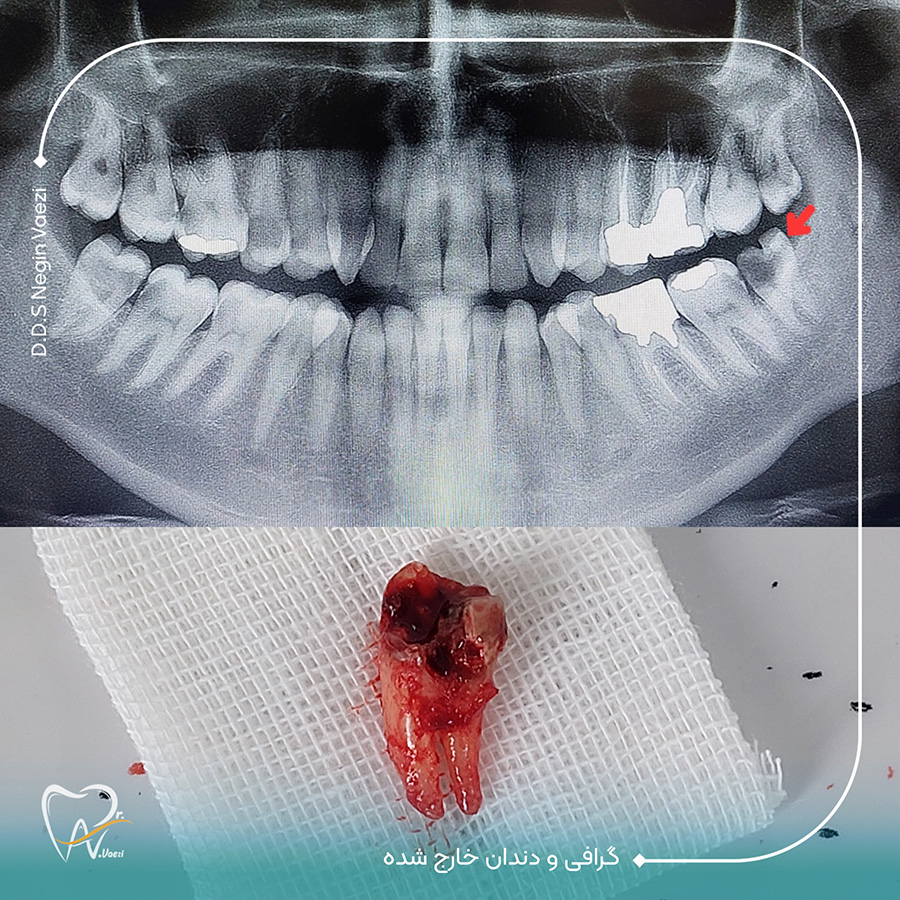

نمونه کارهای جراحی دندان عقل بسیار زیاد هست و تنها تعدادی محدودی از این نمونه کارهای جراحی دندان عقل رو در سایت قرار داده ایم. شما می توانید برای مشاهده نمونه کارهای بیشتر حتما پیج اینستاگرام دکتر نگین واعظی رو دنبال کنید. خب در این نمونه کار که تصویر اون رو در زیر می بینید جراحی دندان عقل توسط دکتر نگین واعظی صورت گرفته است.

در این نمونه کار، دندان عقل بیمار بهصورت کامل رویش یافته بود اما دچار پوسیدگی شدید شده و برای بیمار ایجاد درد و ناراحتی کرده بود. با بررسی گرافی، مشخص شد که امکان ترمیم وجود ندارد و باید دندان بهطور کامل خارج شود.

🔹 این جراحی توسط دکتر نگین واعظی با بیحسی موضعی و در مدت زمان کوتاهی انجام گرفت.

تصویر قبل و بعد از جراحی